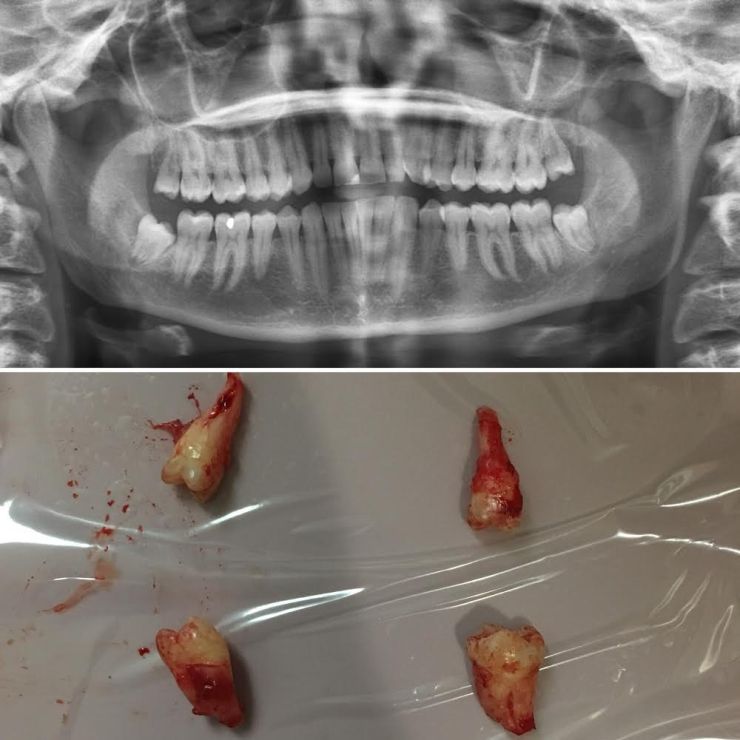

Bloody teeth! It is often best to extract wisdom teeth early as it makes the procedure less traumatic. In this case, minimal sedation was required – nitrous oxide.